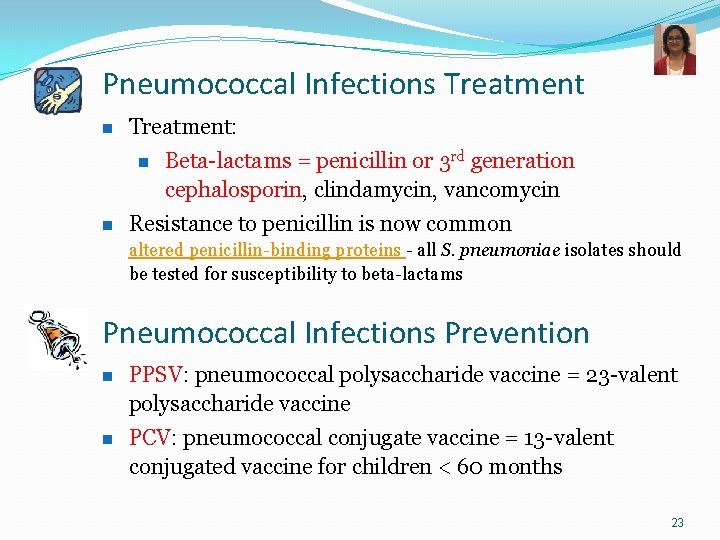

Pneumococcal Infections Treatment n Treatment: n n Beta-lactams = penicillin or 3 rd generation cephalosporin, clindamycin, vancomycin Resistance to penicillin is now common altered penicillin-binding proteins - all S. pneumoniae isolates should be tested for susceptibility to beta-lactams Pneumococcal Infections Prevention n PPSV: pneumococcal polysaccharide vaccine = 23 -valent polysaccharide vaccine n PCV: pneumococcal conjugate vaccine = 13 -valent conjugated vaccine for children < 60 months 23